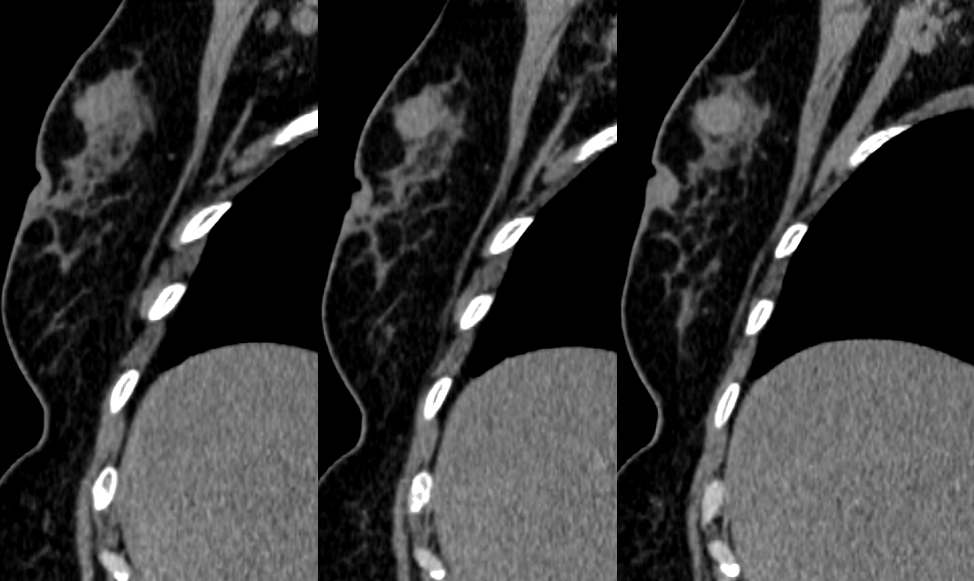

MG/CT:

乳腺炎:包括急、慢性乳腺炎和乳腺脓肿,多见于产后哺乳期妇女,急性乳腺炎常有典型的临床症状-红、肿、热、痛;若治疗不及时可形成慢性乳腺炎或乳腺脓肿。MG 表现片状致密影,边缘模糊,患处皮肤水肿增厚,皮下脂肪层模糊;MRI-T1WI 表现为片状低信号,T2WI 高信号,信号强度不均匀,边缘模糊,皮肤水肿、增厚,增强 MRI 通常表现为轻至中度强化,且以延迟强化为主。